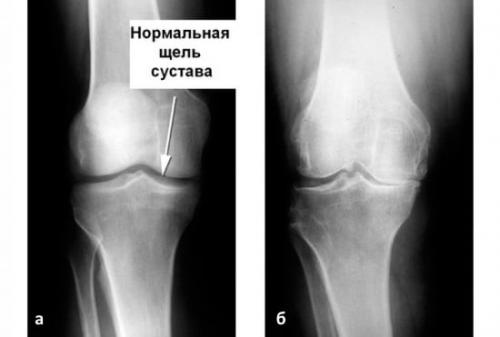

На изображении справа заметно сращение суставной щели.

- Гонартроз поражает коленный сустав. Дегенеративно-дистрофическому изменению подвергается гиалиновый покров сустава, сужается суставная щель. Происходят деформация и перестроение костной ткани с образованием шипов – остеофитов. Нарушает подвижность колена.